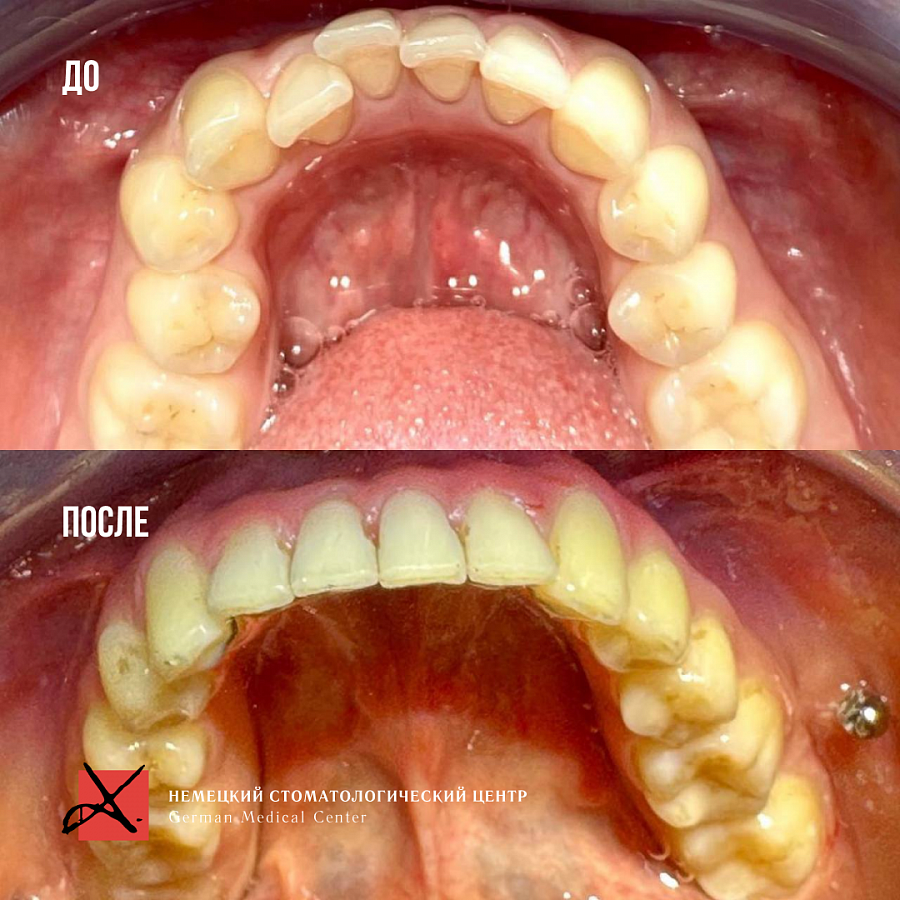

Комплексное гнатологическое и ортодонтическое лечение

Искривление зубных рядов, которое в свою очередь вызывало ряд гнатологических проблем: головная боль, боль в шейном отделе, боль ВНЧС, стираемость эмали и т.д.

Было проведено комплексное гнатологическое и ортодонтичечкое лечение. В результате пациент получил не только красивые ровные зубы, но и избавился от всех сопутствующих проблем.